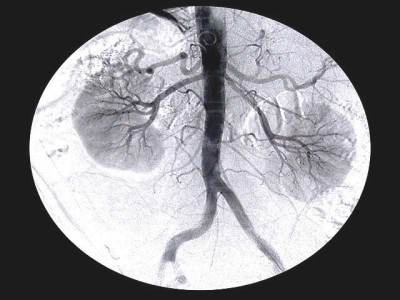

Incidence of kidney failure shows sharp increase

18,697 dialysis cases reported in 2018